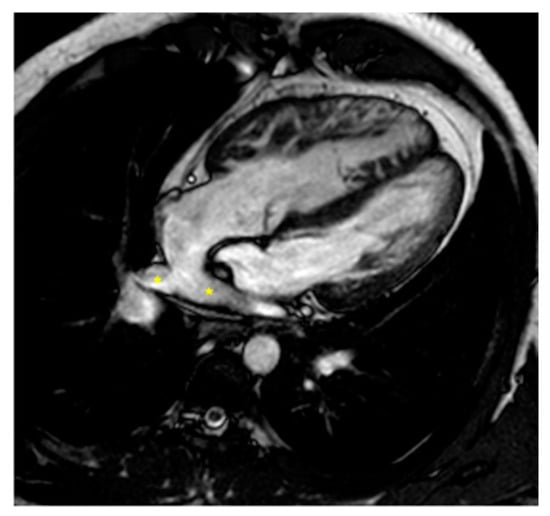

2.2.1. Dextro-Transposition of the Great Arteries (D-TGA)

Atrial Switch Operation and the Role of CMR Imaging

Arterial Switch Operation and the Role of CMR Imaging